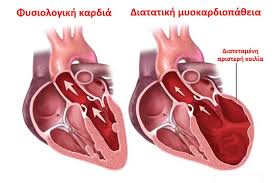

Διάταση δεξιάς κοιλίας ως προγνωστικός παράγοντας θνητότητας σε ασθενείς με Covid-19 λοίμωξη

Οι Ιατροί της Θεραπευτικής Κλινικής της Ιατρικής Σχολής του Εθνικού και Καποδιστριακού Πανεπιστημίου Αθηνών, Κίμων Σταματελόπουλος, Ιωάννης Παρασκευαϊδης, Ιωάννης Κανακάκης και Θάνος Δημόπουλος (Πρύτανης ΕΚΠΑ), ανέλυσαν πρόσφατα δεδομένα από τη διεθνή βιβλιογραφία σχετικά με την προγνωστική σημασία της διάτασης της δεξιάς κοιλίας της καρδιάς...